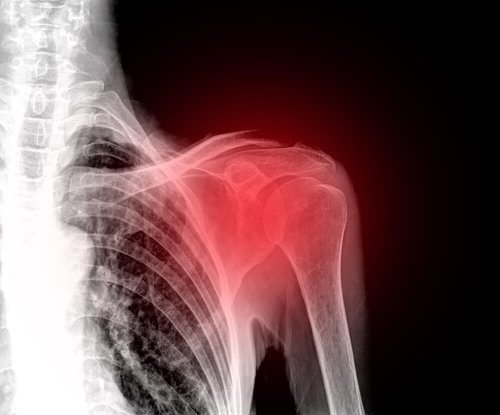

O ombro congelado é uma situação patológica e traumatológica da articulação do ombro. Também é conhecido como “capsulite adesiva”, porque o mecanismo final de produção de sintomas é a inflamação da cápsula do ombro.

Para entender isso, temos que revisar como o ombro é constituído. É uma articulação onde o úmero, a clavícula e a escápula entram em contato como ossos, todos cercados por um tecido mole que forma a cápsula e os envolve. Essa cápsula é a que engrossa no ombro congelado.